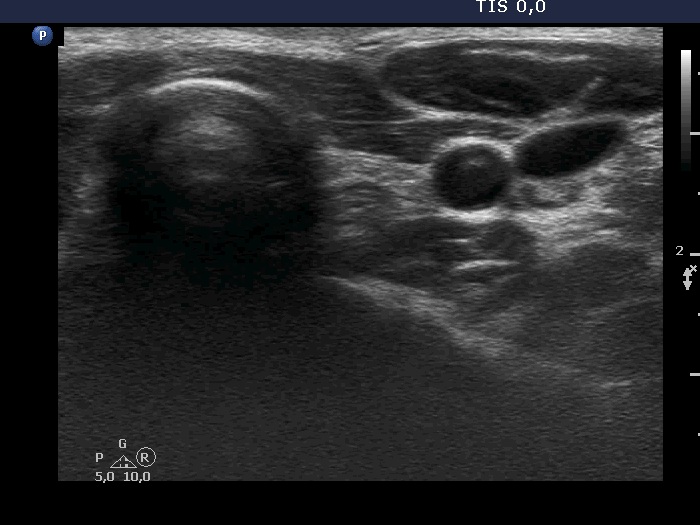

Case 1738 (ultrasonographic picture 8)

Left lobe, transverse scan. Connective tissue replaces the thyroid parenchyma. The round hypoechoic mass in the dorsal part of the thyroid bed is the esophagus.